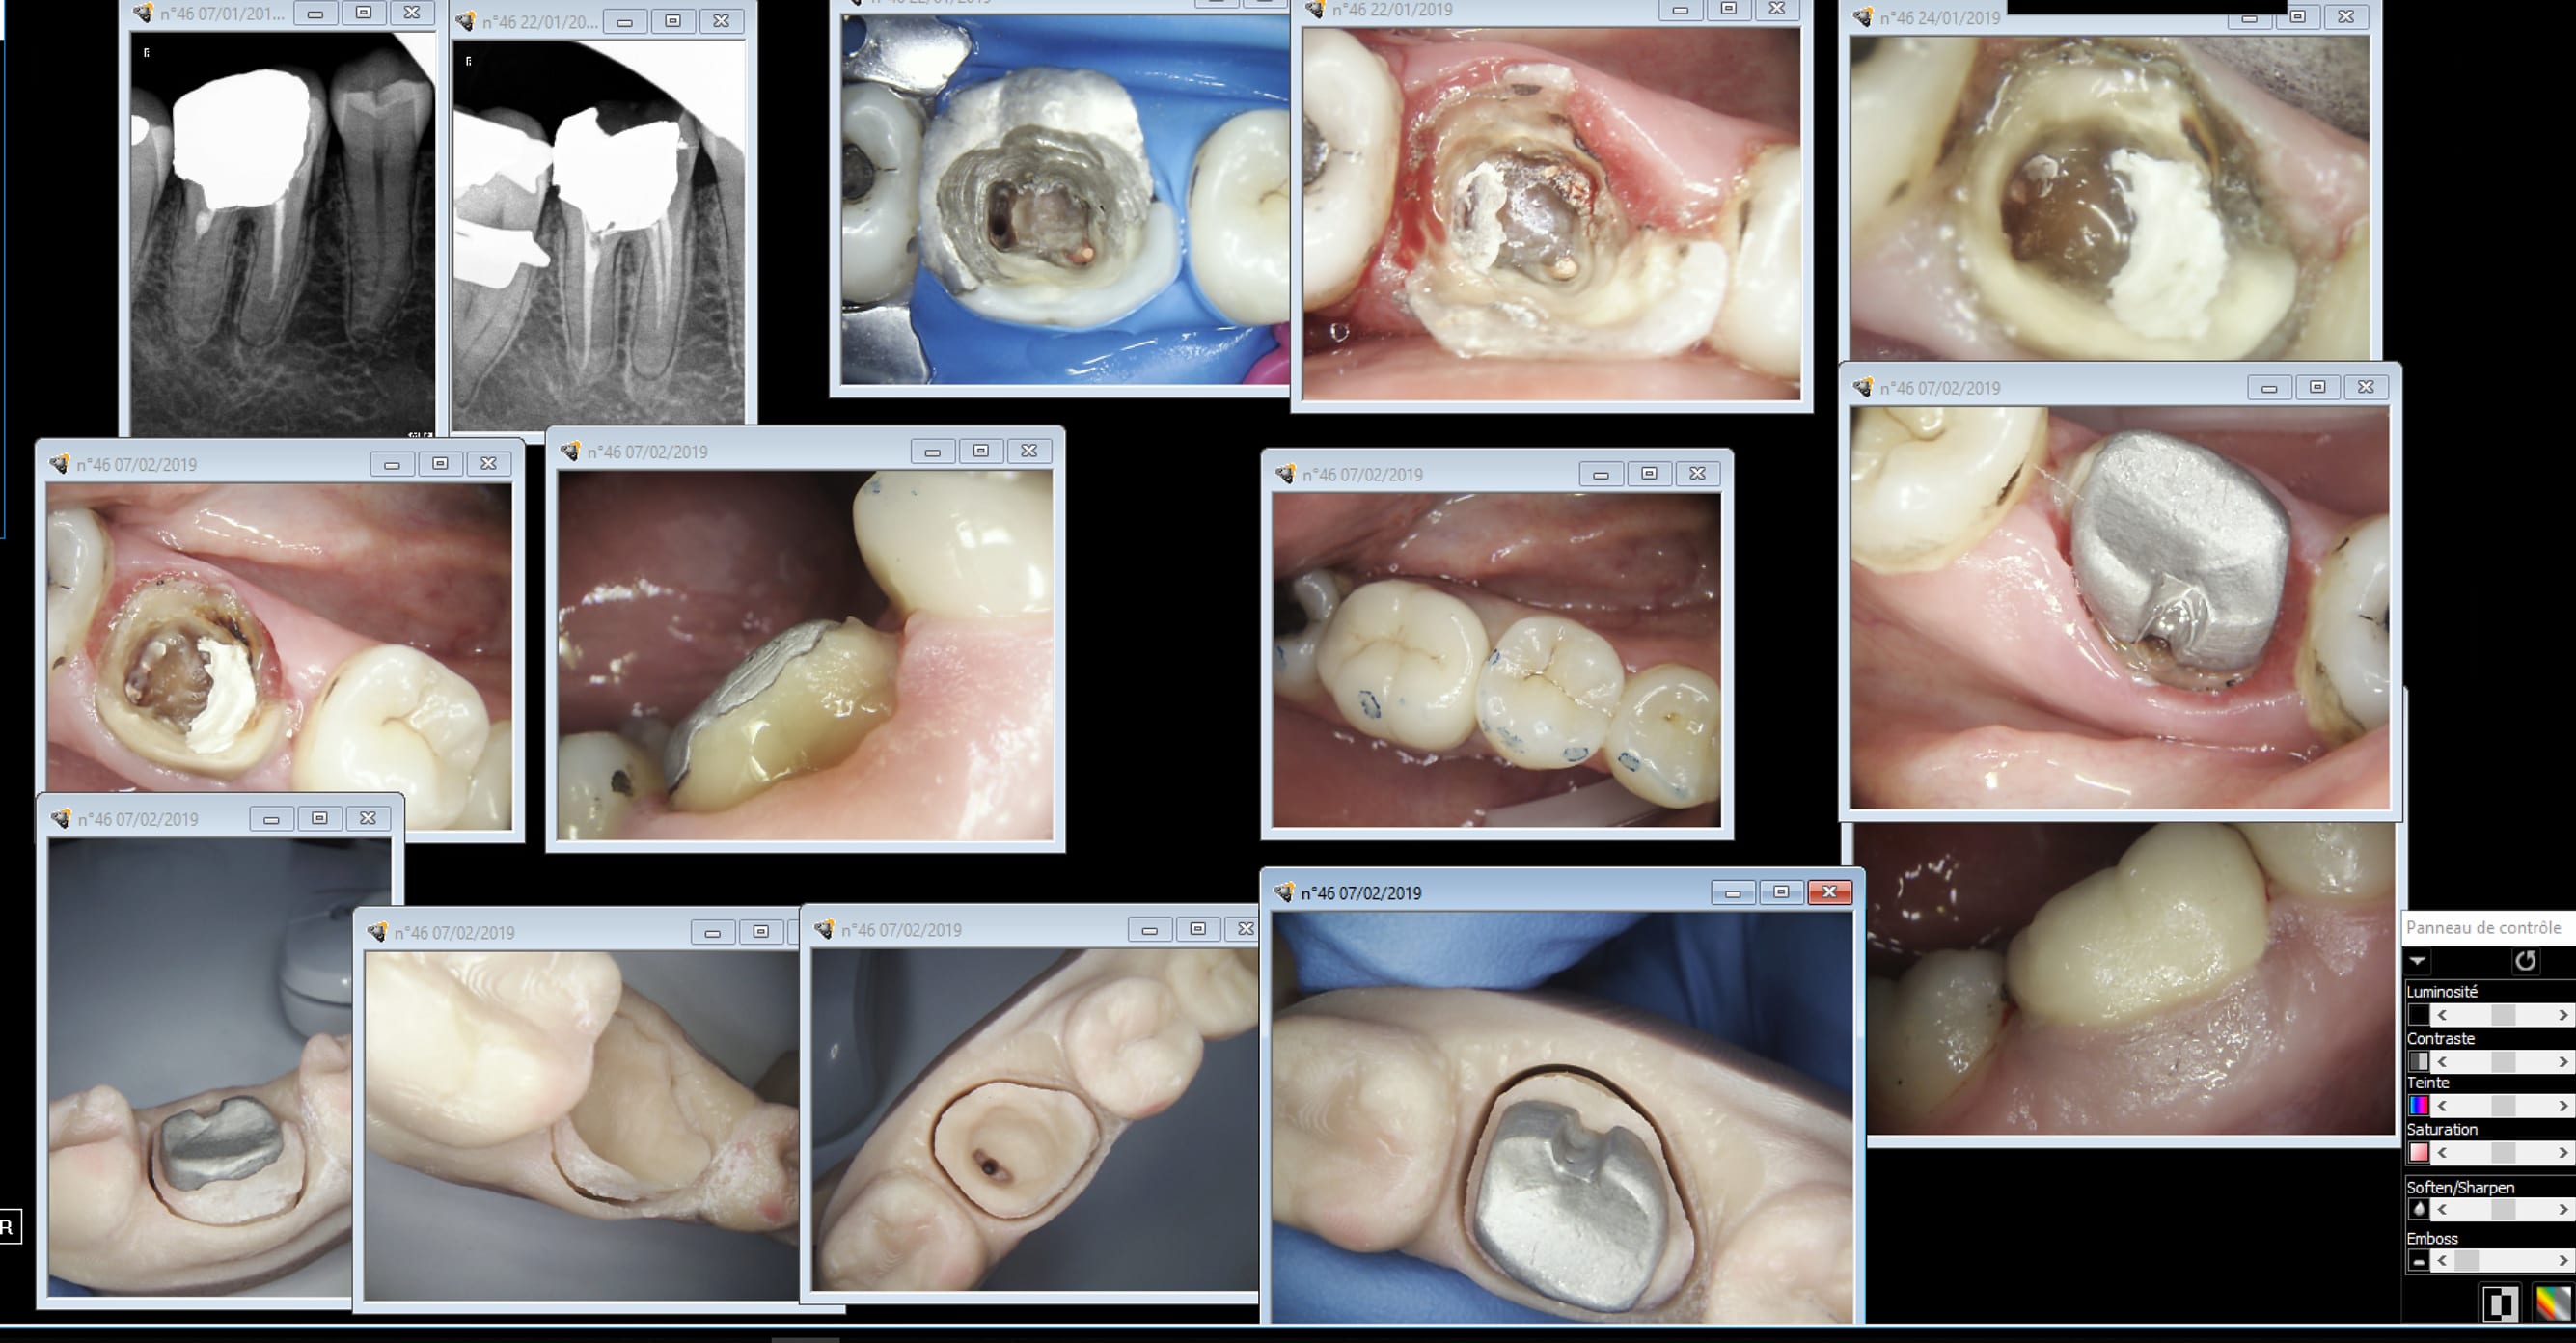

Again. Et encore j'ai merdé j'ai laissé des parois trop fines en vestibulaire. Top concentré sur la daube sous gingivale en lingual. En platre ca aurait pété.

Une semaine après au laser ca ne saigne pas. Au bistouri électrique c'est du steack haché sanguinolant. .

L'empreinte.